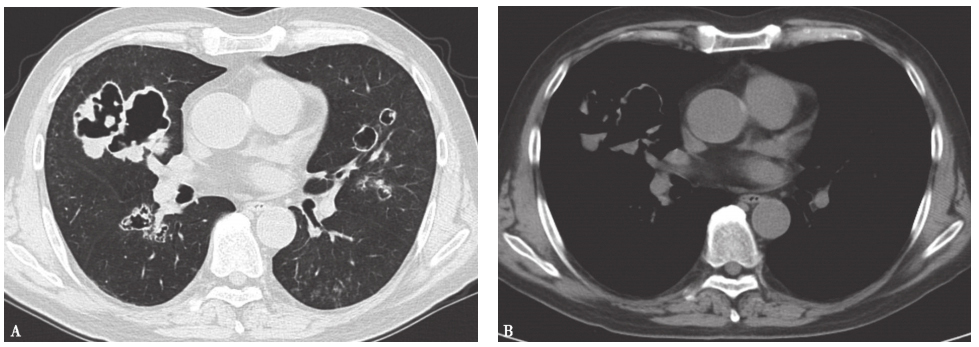

图4 韦格纳肉芽肿胸部CT表现

胸部CT平扫可见双肺多发空洞性改变,个别空洞伴液平(蔡后荣教授提供)

图6 肺鳞癌胸部影像学表现

女性患者,86岁,痰中带血5个月。胸部X线片(A)可见左上叶巨大厚壁空洞,内壁凸凹不平,CT(B)可见左上叶巨大厚壁空洞,内壁凸凹不平,并见液平。病理诊断为肺鳞癌